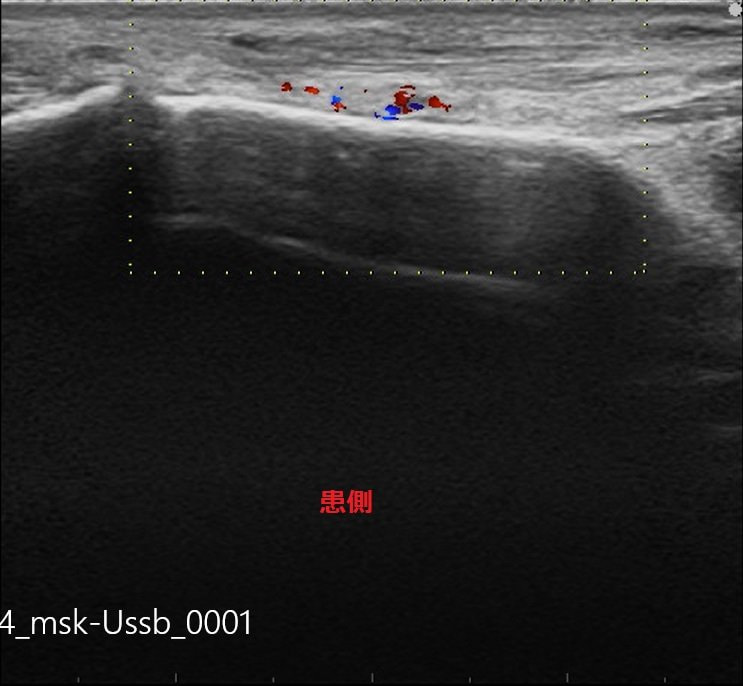

今日の患者様は柔道での日々の稽古、走り込みが続き、歩行時、体重負荷に「足の甲が痛い」と御来院。

足の甲の一番高い所に圧痛が強く、場所的に中足骨の疲労骨折が疑われます。

今回はエコー検査を行い、まだ疲労骨折にはいたっていないですが、

このまま無理に動いていると、必ず疲労骨折を発症する為、安静・治療となりました。

中足骨骨膜炎-患側.jpg